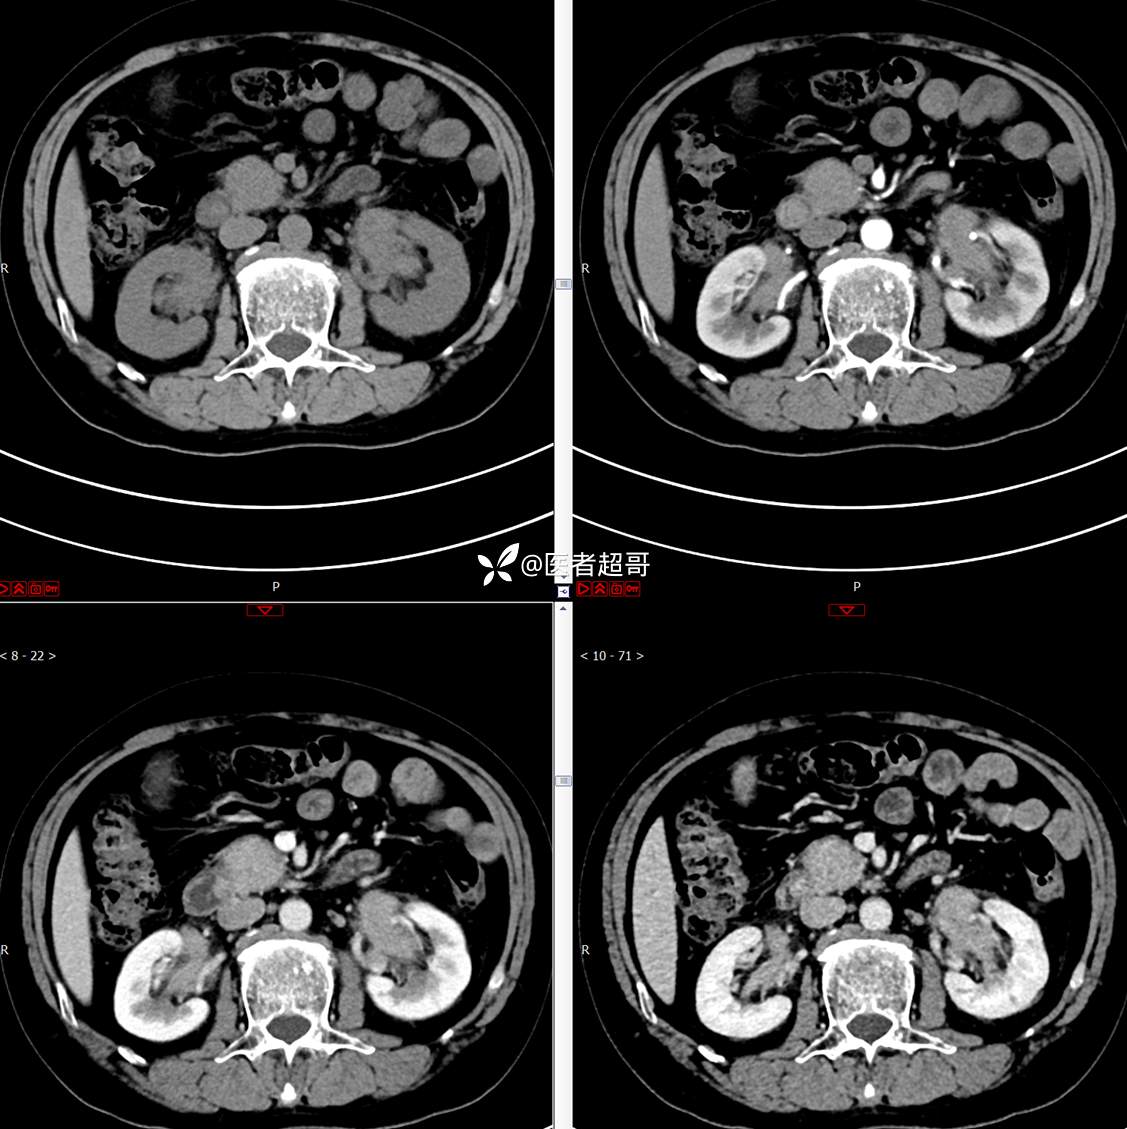

【影诊笔记772】腹痛就诊,发现肾脏病变,CT、MRI齐全,请高诊!

男,63岁 0200825 01

主 诉:间断腹痛15天

现病史:患者15天前无明显原因及诱因出现腹部疼痛不适,呈间断性钝痛,右下腹为著,无尿频、尿急、尿不尽,无发热、寒战,无腹胀。于市中心卫生院住院治疗,超声示:胰头低回声包块,胆系扩张,左肾囊肿,胆囊壁毛糙,胆囊内胆汁淤积。患者为求进一步诊治,遂以“肾盂肿瘤”收入院,患者自发病以来,神志清,精神可,饮食睡眠可,大便无明显异常,近期体重无明显增减。

既往史:既往体健